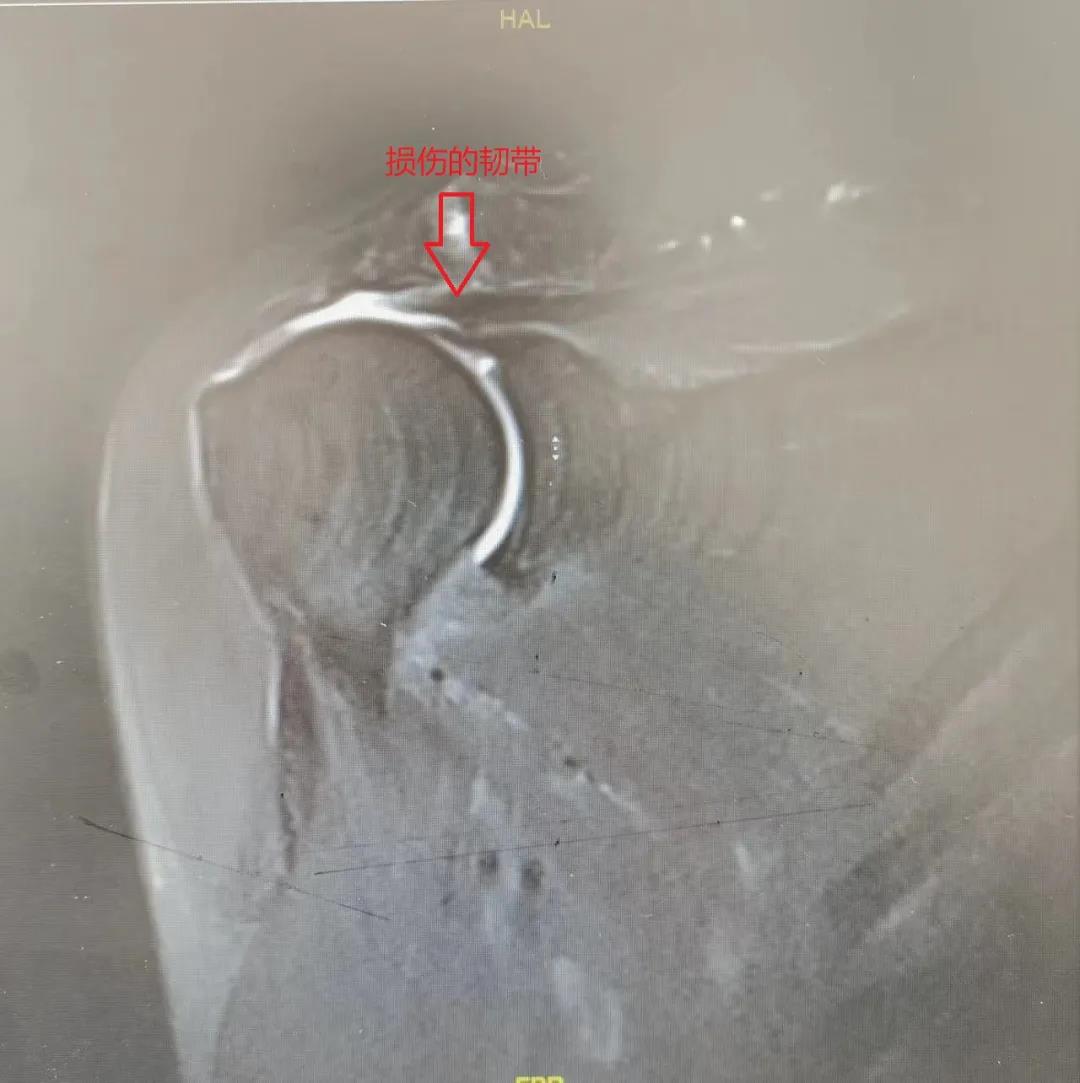

患者周先生磁共振MRI检查

南昌大学第二附属医院骨科专家郝亮博士,李晨博士结合周先生病情,诊断为1、右肩袖损伤(撕裂)2、右肩峰撞击征,并制定了手术方案。